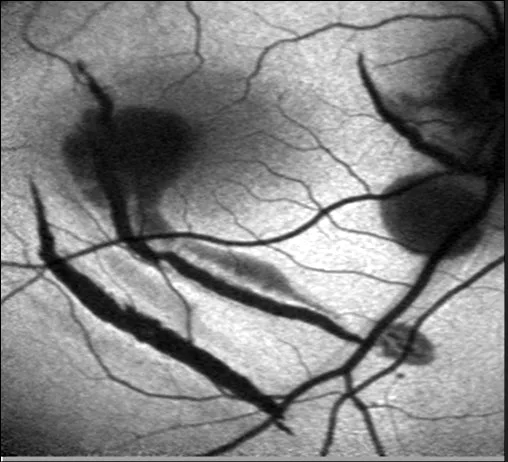

Le même œil scanné lors de visites ultérieures (C : sans APS, ni Autorescan)

L’inclinaison de la tête provoque une variabilité significative dans la classification des résultats.